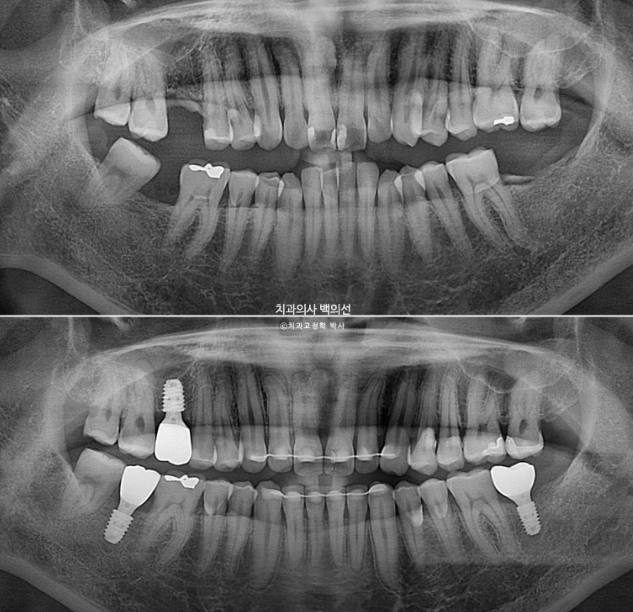

좁아진 공간과 쓰러진 사랑니는 파노라마 엑스레이에서 확인됩니다.

이런 경우 사랑니를 빼버리면 간단하게 해결이 되지만, 이미 상해서 빠진 이가 많은 상태인데다가 사랑니가 잘 나와 대합치과 교합까지 잘 되는 상태라, 사랑니를 최대한 보존해서 쓰기로 합니다.

치근흡수는 없고 뿌리 평행도는 좋습니다.

임플란트는 아름답게 심어졌고 사랑니 교합도 좋습니다.